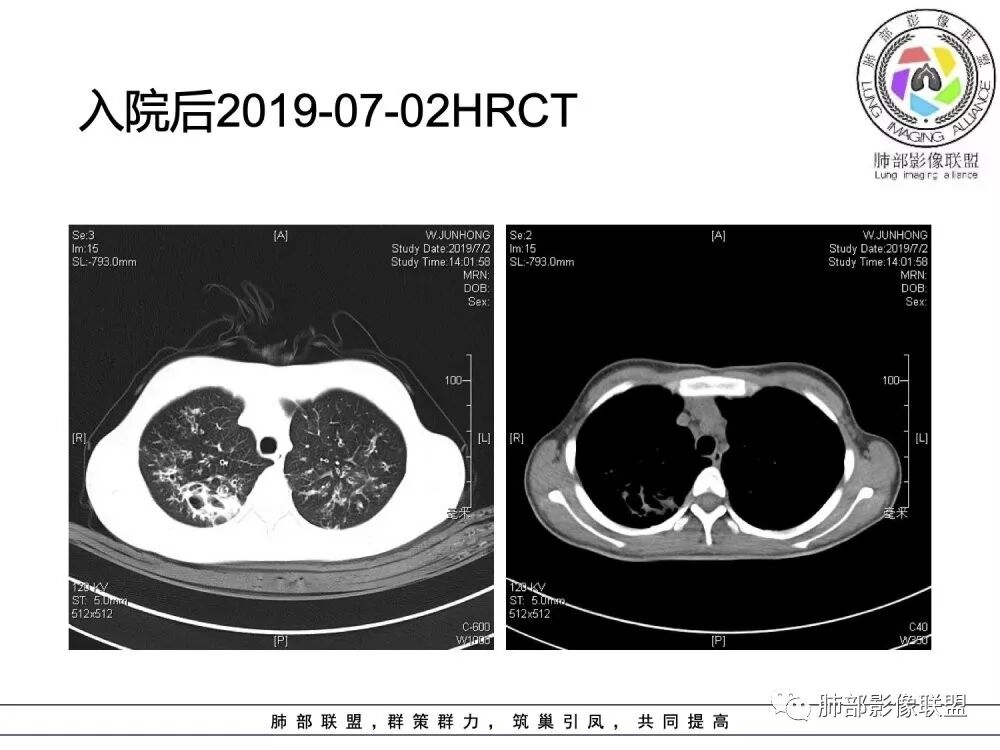

患者青少年女性,以反复咳嗽、咳痰10余年,痰血3年,再发1月余。患者自幼咳嗽、咳痰史,黄白脓痰,曾诊断支气管扩张症,常感乏力,时有腹痛感。有食物药物过敏史。胸CT:病变以双上肺为主,支气管明显扩张,支气管壁可见增厚,可见双轨征,右上肺后段可见囊状改变,并可见片状实变影。诊断考虑:囊性纤维化?鉴别:1 ABPA?2 结核后支气管扩张?

年轻女性,15岁,自幼咳嗽咳痰10余年,痰血三年。两肺呈支扩改变伴小片渗出,双肺上叶为主 。左下见指套状密度偏高影考虑粘液栓,右上部分局限性实变,从病史基本推出诊断,考虑CF。

水晶石头:

病变以双上肺为主,支气管明显扩张,支气管壁可见增厚,可见双轨征 右上肺后段可见囊状改变,并可见片状实变影。患者青少年女性,以反复咳嗽 咳痰10余年,痰血3年,患者自幼咳嗽 咳痰史,黄白脓痰,曾诊断支气管扩张症,考虑:囊性纤维化?

患者15岁,女性,反复咳嗽、咳痰10余年,痰血3年,再发1月余。有腹痛、食物药物过敏史。胸CT:病变双上肺为主,支气管明显扩张,支气管壁可见增厚,双轨征 ,部分可见囊状改变及片状实变影。诊断考虑:CF?鉴别:ABPA;纤毛运动障碍综合征;DBP等

(1)支气管壁增厚、支气管扩张

可广泛分布于两肺各叶,尤其是两肺上叶多见。支气管扩张主要是轻、中度柱状支气管扩张。支气管壁增厚既可发生于扩张的支气管,也可发生于非扩张的支气管,常为轻度增厚,管壁内外比较光滑。

(3)支气管黏液栓

由于黏液分泌物潴留在气管内形成,依据黏液存留的支气管走向不同而形态各异,多呈圆形、椭圆形、管状或尖端指向肺门的“V”形或“Y”形高密度阴影,密度均匀,边缘光滑锐利,CT值一般为15±10HU,但存留较久的黏液栓CT值可高达40~80HU,增强扫描无强化。

(4)薄壁含气囊腔

因支气管扩张、气肿性肺大泡及间质性气囊肿形成大小不一之囊腔,与支气管相关。